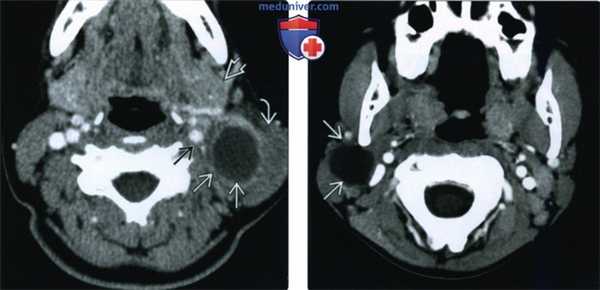

(Слева) При аксиальной КТ с КУ визуализируется гиподенсное объемное образование с ровными краями, лежащее сзади от поднижнечелюстной железы, отклоняющее левую грудино-ключично-сосцевидную мышцу в сторону и кзади, а сосудистый пучок, покрытый сонным влагалищем, - кнутри. Контрастное усиление в виде тонкого «ободка» является признаком хронического воспаления и лимфоидной гиперплазии стенки кисты.

(Справа) При аксиальной КТ с КУ в области угла нижней челюсти справа визуализируется объемное образование, выглядящее кистозным, не накапливающее контраст. Это наиболее типичная локализация кист второй жаберной щели.